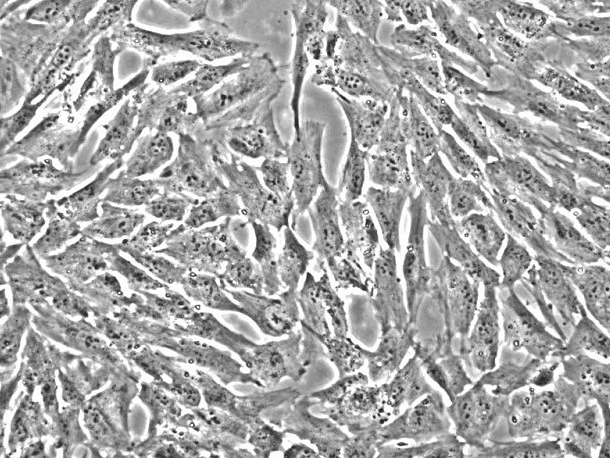

产品名称:HISMC;人肠平滑肌细胞(原代细胞)

来自ScienCell研究实验室的HISMC与人体肠道分离。HISMC在*代冷冻保存并冷冻。每个小瓶含有>5×10^5个细胞,1ml体积。HISMC的特征在于免疫荧光,具有对α-平滑肌肌动蛋白和结蛋白特异的抗体。HISMC对HIV-1,HBV,HCV,支原体,细菌,酵母和真菌均为阴性。在ScienCell研究实验室提供的条件下,HISMC保证进一步扩大15次人口倍增。

平滑肌收缩是胃肠运动的基本事件。尽管尚未定义激发 - 收缩偶联的许多生化机制,但已知细胞溶质Ca 2+是偶联现象中的必要组分。人体肠道的炎症导致平滑肌特异性肌动蛋白水平增加,这反过来促进平滑肌层的增厚。增加的平滑肌肌动蛋白可能影响力的产生,并进一步证明发炎肠道中平滑肌细胞的可塑性[1]。研究还表明,人体肠道平滑肌细胞(HISMC)通过释放IL-6对IL-1β和TNF-α刺激有反应,这可能显着促进整体全身炎症反应[2]。